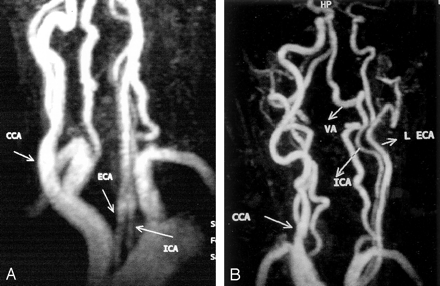

An MRA study clearly revealed a low bifurcation of the common carotid artery on the right side, the left common carotid artery was absent, and the internal and external carotid arteries arose directly from separate origins on the aortic arch (Fig). An additional MRA study of the intracranial arteries did not show any associated intracranial arterial lesion or variation.

Contrast-enhanced 3D MRA images (5.2/2.1, 25° flip angle)of the neck show the independent origins of the left internal carotid artery (ICA) and external carotid arteries (ECA and L ECA) that arise directly from the aortic arch. Note that a low carotid bifurcation (CCA) is associated on the right side. VA indicates the left vertebral artery.